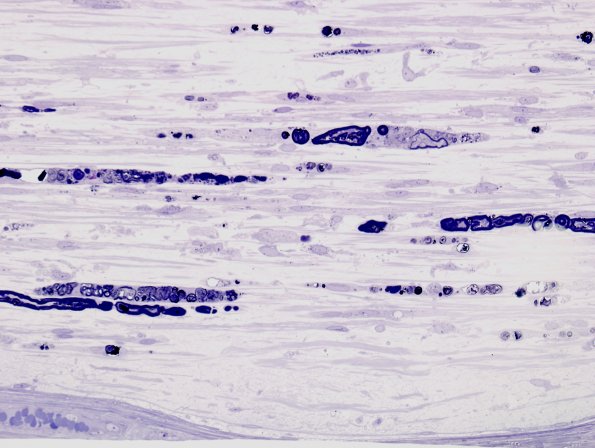

16B1,2 The same nerve as image #16A1 shown in longitudinal sections showing degenerating axon and myelin debris in Schwann cell ovoids. (plastic sections)